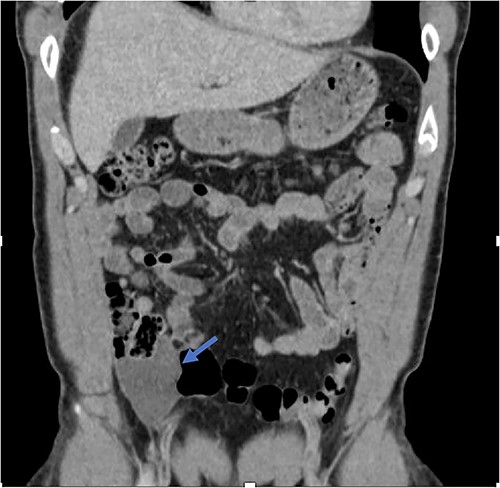

An exploratory laparotomy with a midline incision was performed. Upon inspection of the abdominal cavity, there was no evidence of metastatic disease to the peritoneum, omentum, or liver. A perforated mucinous mass with mucinous collection was identified in the right lower quadrant by the appendix with an additional mucinous collection in the pelvis. Given the appendiceal and cecal involvement, the decision was made to perform a right hemicolectomy and primary anastomosis. Given that this was favored to be a malignant process intraoperatively, the decision was made to perform a right hemicolectomy over a limited ileocolic resection. Lymph nodes were also included due to the extent of the surgical resection. The specimens were sent to pathology. The abdomen was further inspected and subsequently closed (Figs 3–5). The patient tolerated the procedure well, was extubated in the operating room, and recovered in the post-anesthesia care unit in stable condition. The patient was observed postoperatively and was discharged home on postoperative Day 8. The duration of follow-up is 4 months without clinical concerns during follow-up. The final pathology of the specimens revealed LAMN with perforation and associated calcifications. The proximal and distal resection margins were free of neoplasia, and 42 lymph nodes were negative for tumor. There was presence of acellular mucin in the tissue sample, suggesting a favorable prognosis according to previous studies demonstrating that 96% of patients with acellular extra-appendiceal mucin were disease-free at 52 months [5]. Follow-up via surveillance magnetic resonance imaging (MRI) every 6 months, and colonoscopy were recommended. The patient was referred for blood testing, including the tumor marker carcinoembryonic antigen (CEA), which has been unremarkable.

Perforated mucinous mass at the base of the appendix (blue arrow).